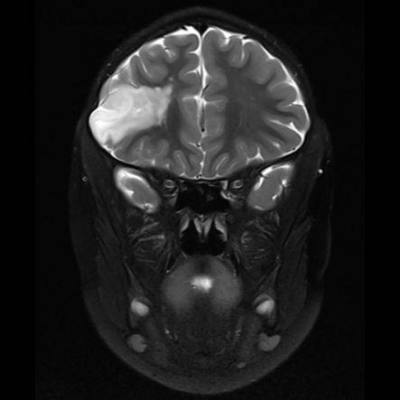

DNET:Özellikle erkek çocuk ve nöbet öyküsüyle gelen hasta kortikal yerleşim ve t1 ağırlıklı serilerde hipointens t2a ve flair serilerde ise hiperintens görülmesi bu tanıma uymaktadır. Hastaların 5’te birinde frontal lobda da tutulum olabilir. Lezyon çevresinde ödem ya da içerisinde kalsifik odak izlenmemiştir:

DNET:Özellikle erkek çocuk ve nöbet öyküsüyle gelen hasta kortikal yerleşim ve t1 ağırlıklı serilerde hipointens t2a ve flair serilerde ise hiperintens görülmesi bu tanıma uymaktadır. Hastaların 5’te birinde frontal lobda da tutulum olabilir. Lezyon çevresinde ödem ya da içerisinde kalsifik odak izlenmemiştir.